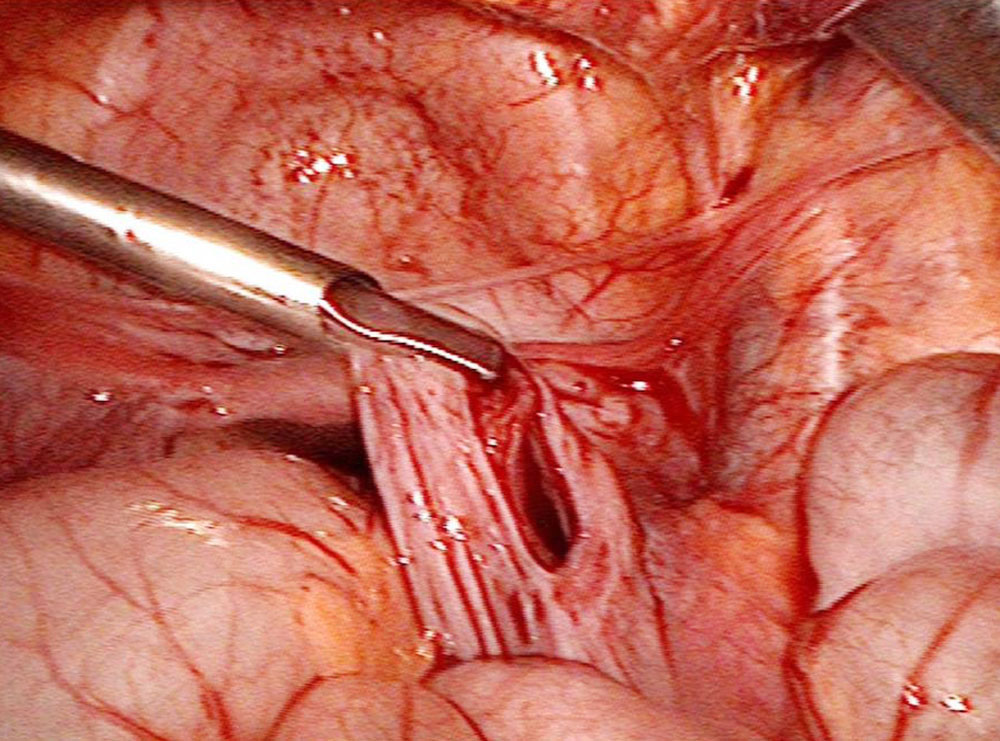

Surgical resection is an important component in the treatment of a cystic lymphatic malformation (hereafter “LM”). If an LM can be completely removed, resection will be chosen in many cases. This is true for limited lymphatic malformations in the skin and subcutaneous area or for retroperitoneal LM, which can sometimes be completely removed laparoscopically.

However, surgery can often only achieve partial removal without injuring important structures. It nevertheless has its place in the therapeutic process when the goal is to bring an LM to the “control” stage. In the facial region, sparing the branches of the facial nerve is important, so the procedure of intraoperative neuromonitoring is used here, as well as in the neck region, where the accessory nerve and the cervical and brachial plexus must remain uninjured.